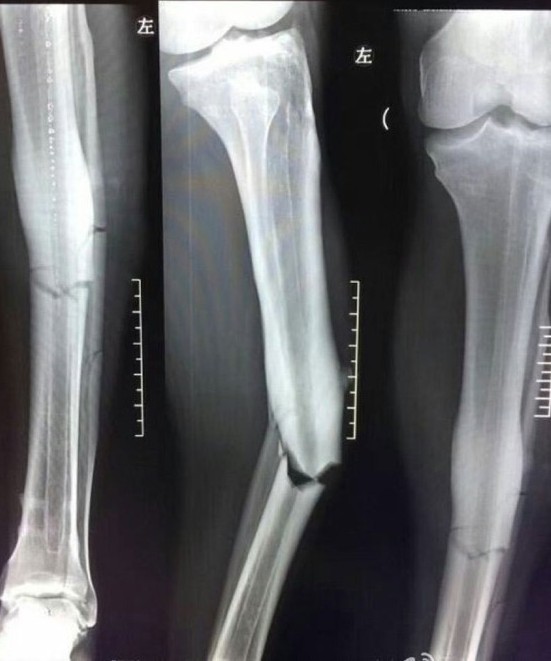

Çin'de ayağı kırılan Demba Ba için gelen Fransız doktorlar yıldız oyuncuya 3 saat sürecek olan bir operasyon yapacak.

Çin Ligi'nde Shanghai Shenhua formasıyla çıktığı son karşılaşmada sakatlanan ve futbol hayatı tehlikeye giren Demba Ba'nın tedavisi için Fransa'dan doktorların geleceği bildirildi.

Hafta sonunda Shanghai'ye gelecek olan doktorların Çin'deki sağlık ekibiyle birlikte oyuncuyu ameliyata alacakları; Demba Ba'nın raporlarını inceleyen Fransız sağlık ekibinin daha olumlu ifadeler kullandığı kaydedildi.

SporX'te yer alan habere göre; 3 saatlik bir operasyonla ameliyata girecek olan Demba Ba'nın rehabilitasyon süresinde ise Fransa'da olacağı yazıldı.

Ülke basınında yer alan iddiaya göre, Demba Ba'nın tedavisi için seferberlik ilan edildi. Fransa'dan gelecek olan yabancı doktorların Demba Ba için cerrahi operasyon yapacağı vurgulandı.

Çin'den Demba Ba için sık sık rapor alan Fransız uzmanların buraya gelmesinin nedeninin ise yolculuk süresinin fazla olması gösterildi.

Demba Ba'nın çekilen röntgeninde ayağının görüntüsü bu şekildeydi. Demba Ba'nın ameliyat durumuna göre futbola veda edebileceği belirtiliyor.